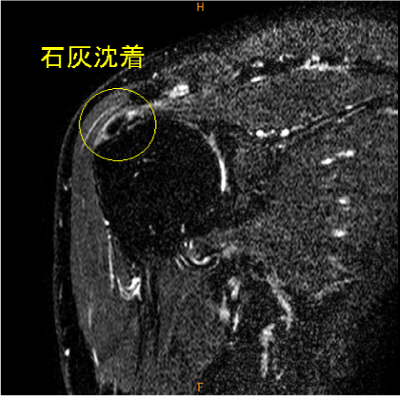

MRI所見

陳旧性石灰沈着性腱板炎のために肩峰下の擦れを生じていると考えられる症例。

石灰沈着は脂肪抑制T2, T2*

画像で気がつきやすい。

診断

陳旧性石灰沈着性腱板炎、擦れ、断裂(-)